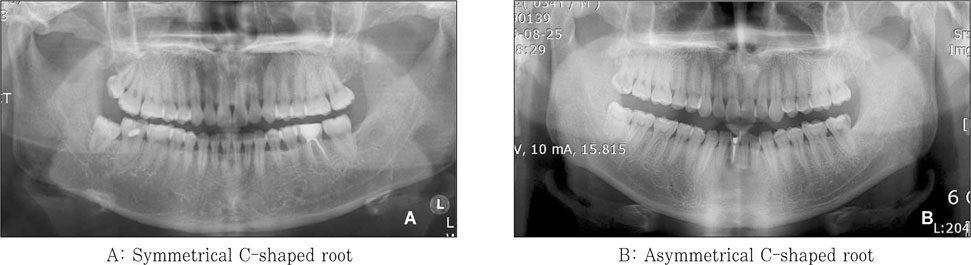

Figure 4

Bilateral symmetry of the C-shaped root canal.

Figure 4 Bilateral symmetry of the C-shaped root canal.